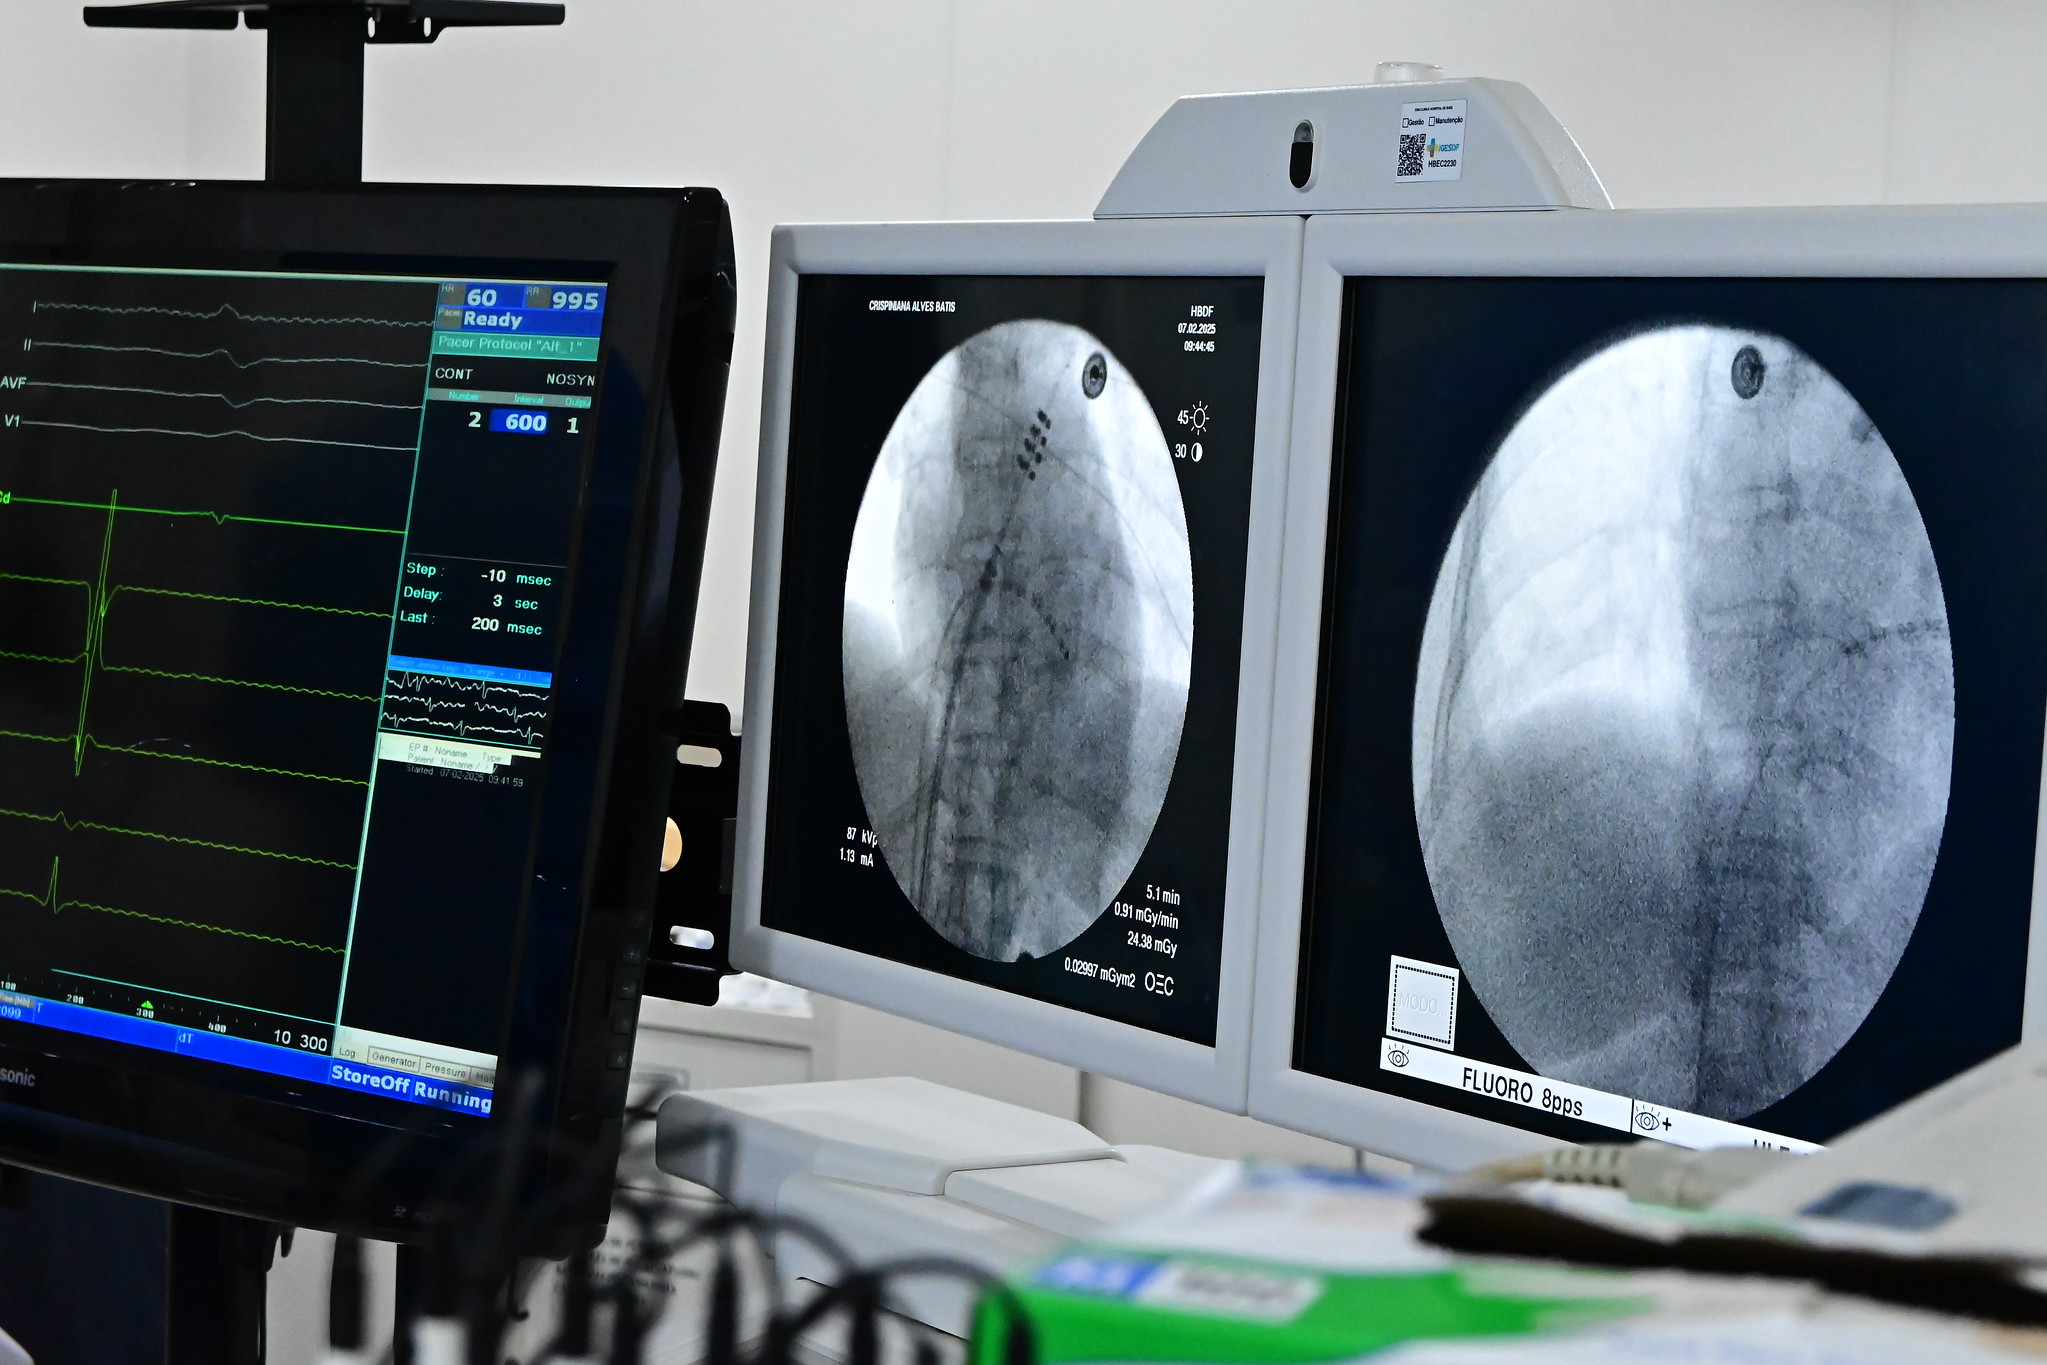

Na última sexta-feira (07), o Hospital de Base do DF tornou-se a primeira unidade de saúde 100% SUS a realizar um procedimento inovador para o tratamento de arritmias cardíacas com a ablação e aplicação de pulso de elétrons (PFA). Essa técnica minimamente invasiva não exige centro cirúrgico, UTI, anestesia geral nem internação prolongada, representando um avanço no tratamento da doença dentro da rede pública de saúde.

permite a realização da ablação com mais segurança e eficiência. O procedimento, chamado ablação de fibrilação atrial com aplicação de pulso de elétrons, é um marco no tratamento da arritmia e já tem mostrado resultados promissores”, destaca.

“O que antes levava 8 a 10 horas e exigia UTI, agora pode ser realizado em cerca de 55 minutos. O paciente pode ser encaminhado à enfermaria e recebe alta em poucos dias, o que reduz riscos, otimiza o atendimento e diminui custos”, explica o cardiologista Henrique Cesar.

Os primeiros dois pacientes submetidos à nova técnica no Hospital de Base foram um homem e uma mulher, ambos hipertensos, sendo que um deles já havia sofrido um infarto anteriormente. A eletrofisiologista relata que os procedimentos foram concluídos com sucesso absoluto, sem intercorrências. “O tempo de sala foi significativamente reduzido em comparação com as tecnologias anteriores, o que é um ganho importante tanto para os pacientes quanto para o hospital”, enfatiza.

Uma das principais vantagens da nova técnica é a possibilidade de realizá-la fora do ambiente cirúrgico tradicional, no próprio setor de hemodinâmica, garantindo mais agilidade e segurança para os pacientes.